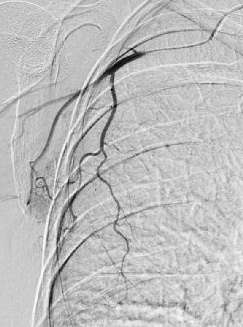

2. 选择性乳腺动脉导管造影术 导管术

C-arm CT扫描或CT血管造影及动脉灌注栓塞和药物灌注前的评估